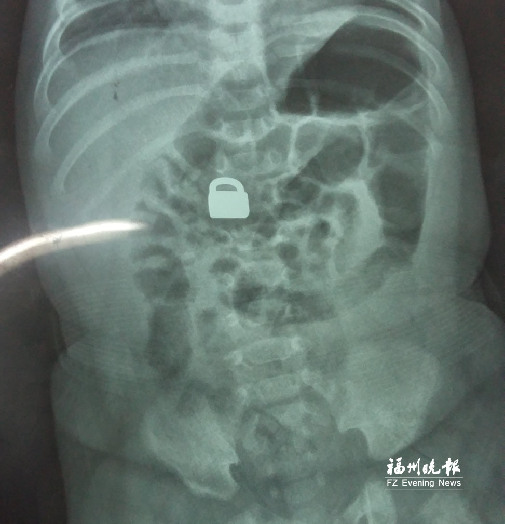

7.25龍巖當(dāng)?shù)蒯t(yī)院拍的X光片顯示,平安鎖在寶寶體內(nèi)。

這名60天大的“神奇寶寶”來(lái)自龍巖,哥哥也只有兩歲。7月25日,兄弟倆的媽媽突然發(fā)現(xiàn)寶寶胸前掛著的平安鎖不見(jiàn)了,便問(wèn)小哥哥是否看到弟弟的平安鎖。小哥哥回答,他把平安鎖塞到弟弟嘴里了。媽媽趕緊檢查寶寶嘴巴,沒(méi)有發(fā)現(xiàn)平安鎖。雖然寶寶沒(méi)有任何癥狀,但媽媽還是帶著他去當(dāng)?shù)蒯t(yī)院檢查。拍片結(jié)果顯示,平安鎖真的在寶寶體內(nèi)。

“X光片顯示,那是一把1.5厘米×0.9厘米的平安鎖,有指甲蓋大小,已經(jīng)到了寶寶的小腸處?!?月28日,陳惠萍見(jiàn)到寶寶時(shí),吃了一驚,“他真的好小,被抱在媽媽懷里,眼睛微微睜開(kāi),我估計(jì)他的世界還是混沌的,沒(méi)想到就已經(jīng)接受了這么大的挑戰(zhàn)?!?/p>